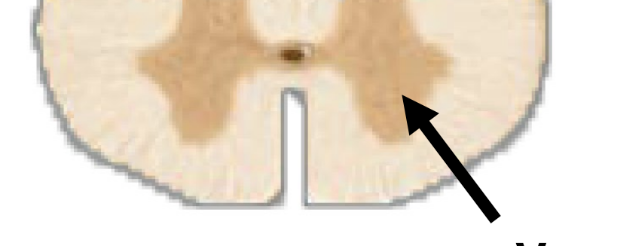

gray matter

• contains unmyelinated cell bodies of neurons

• forms “butterfly” shaped regions

• no myelin → gray color

<ul><li><p>contains unmyelinated cell bodies of neurons</p></li><li><p>forms&nbsp;“butterfly” shaped regions</p></li><li><p>no myelin → gray color</p></li></ul><p></p>

ventral gray horn

cell bodies for motor neurons

<p>cell bodies for motor neurons</p>

dorsal gray horn

cell bodies for sensory neurons

<p>cell bodies for sensory neurons</p>